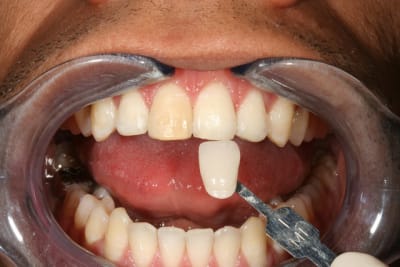

Le protocole est le même que pour une dent dépulpée ; isolation en regard présumé du canal , un peu plus parce que j'ai cherché un moment en plusieurs séances . Perborate , et voilà .

3 séances à 7 jours d'intervalles .

Si on décide d'être le moins invasif , j'ai jugé raisonnable de tenter quand même malgré l'impossibilité de repérage de l'entrée du canal . Faire une facette c'est passer un cap , et je n'ai de prothésiste capable de reproduire les stries visibles sur la photo de départ de tout façon donc je n'ai compté que sur moi même .